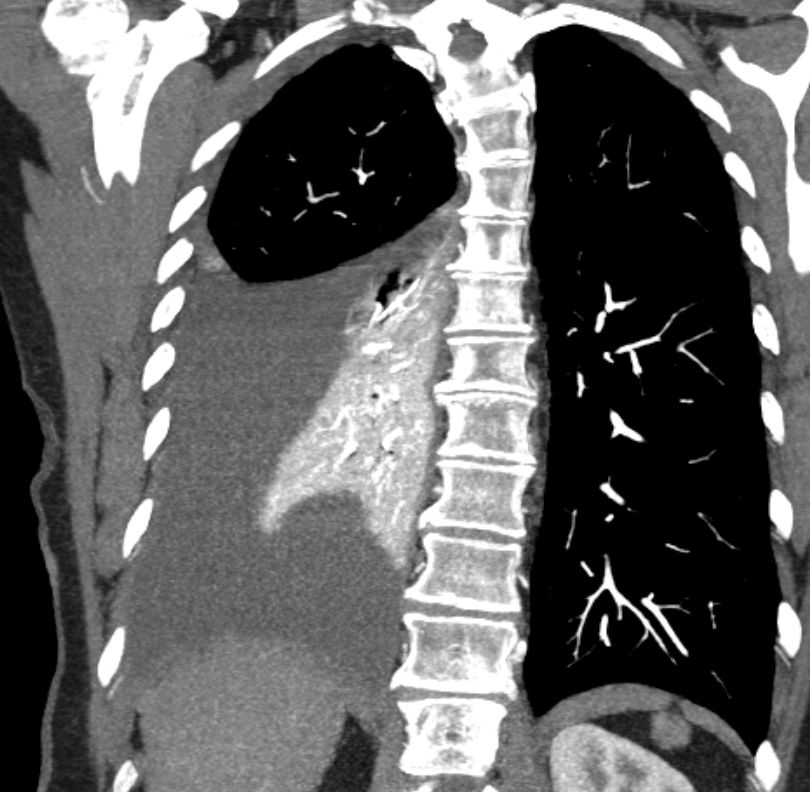

Mamma-CUP 61-jährige Patientin mit Pleuraerguss. Biopsie und Pleurodese Metastasiertes schlecht differenziertes Adenokarzinom ER 12/12; Her2Neu 1+. Mammographie, Mamma-Sonographie, Mamma-MRT o.b.CT Thorax/Abdomen o.B..